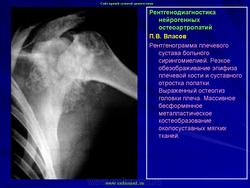

КСС. Артропатия. Сирингомиелия. +

Артропатия.  Сирингомиелия.

Продолжение.